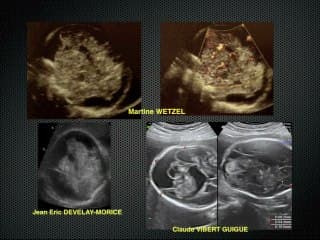

Présentation riche en images de M Althuser des risques d'erreur d'interprétation de la face en échographie.A voir sans modération!